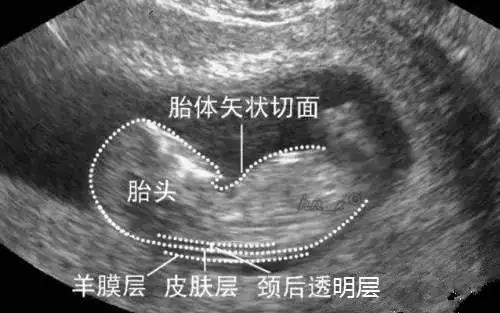

NT指的是“胎儿颈项透明层”,它反映了胎儿颈背部皮肤层与筋膜层之间淋巴液体聚积的厚度,可以称的上是一次畸形小排查。颈项透明层越厚,胎儿发生异常的概率就越大。

医学数据表明在孕11-13+6周这个时间段内,胎儿已经初见人形,头部、躯干、四肢可以分辨出来,在超声下可以观察到胎儿活动,适于早期筛查。更重要的是,在此时间段内,胎儿染色体异常表现出现NT异常的发生率高,排畸率可达98%以上,可以做到早发现早处罝,减少母体创伤。